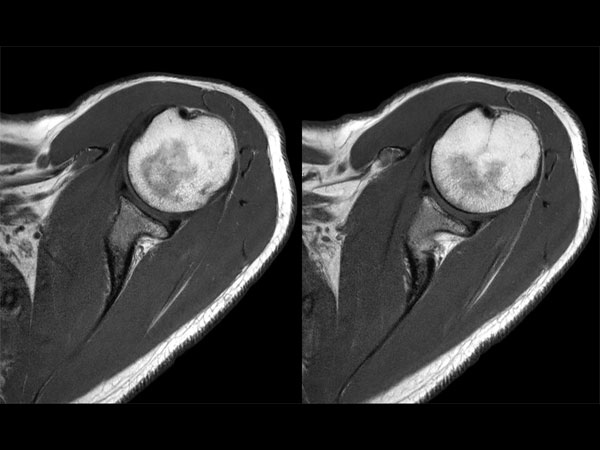

Shoulder imaging with dS Flex coil

• Coil